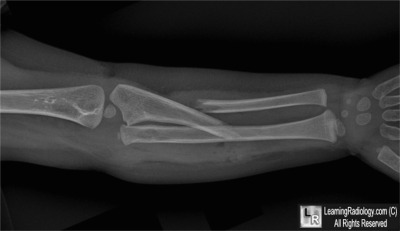

AP Radiograph of Right Forearm

5. Monteggia Fracture

Monteggia Fracture

- Relatively uncommon fracture of the ulna with dislocation of the radial head

- Radial head dislocation may be subtle

- Most are as Monteggia first described them (1814) which are fractures of proximal third of ulna with anterior dislocation of radial head

- Bado type 1 is most common: Fracture of the proximal or middle third of the ulna with anterior dislocation of the radial head